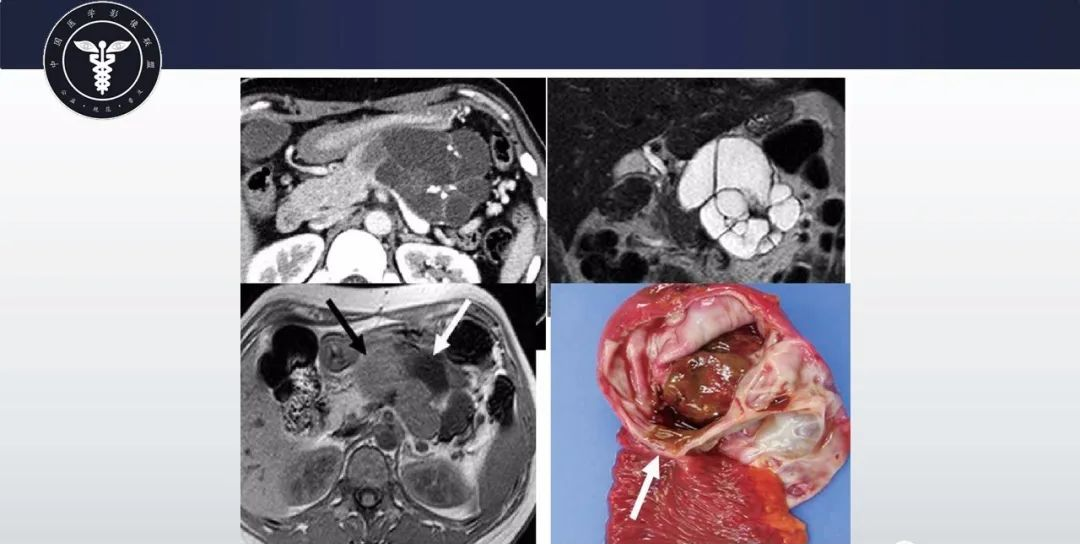

【病例】胰腺血管瘤1例CT及MR影像-4